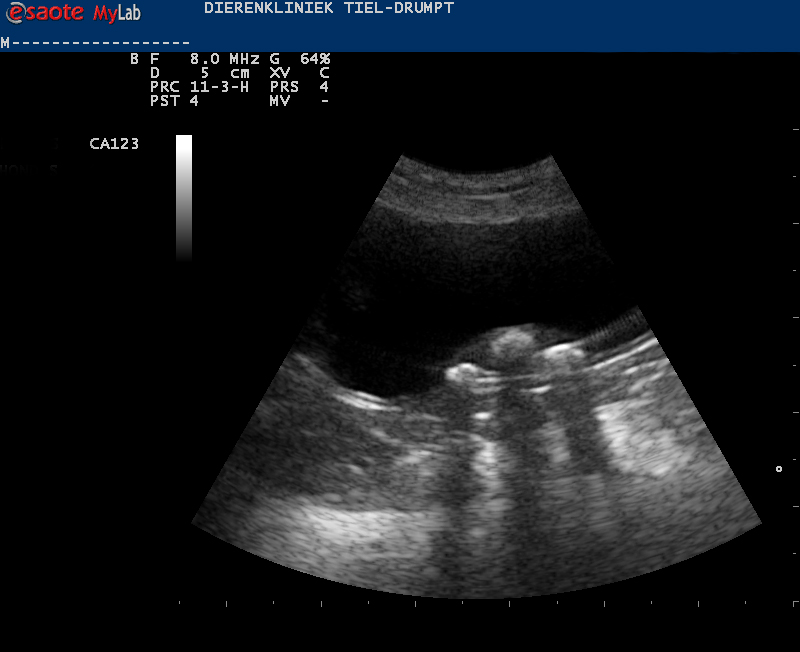

De diagnose van blaasgruis en blaasstenen wordt meestal gesteld via verder onderzoek. Er wordt gestart met een urineonderzoek en met een therapie. Soms is dit onvoldoende om het probleem op te lossen en is er een echo nodig. Met deze echo kan er beter gekeken worden naar de inhoud van de blaas, hoe de blaaswand er uitziet en er kan een punctie gedaan worden van de urine, voor een eventueel bacterieel onderzoek.